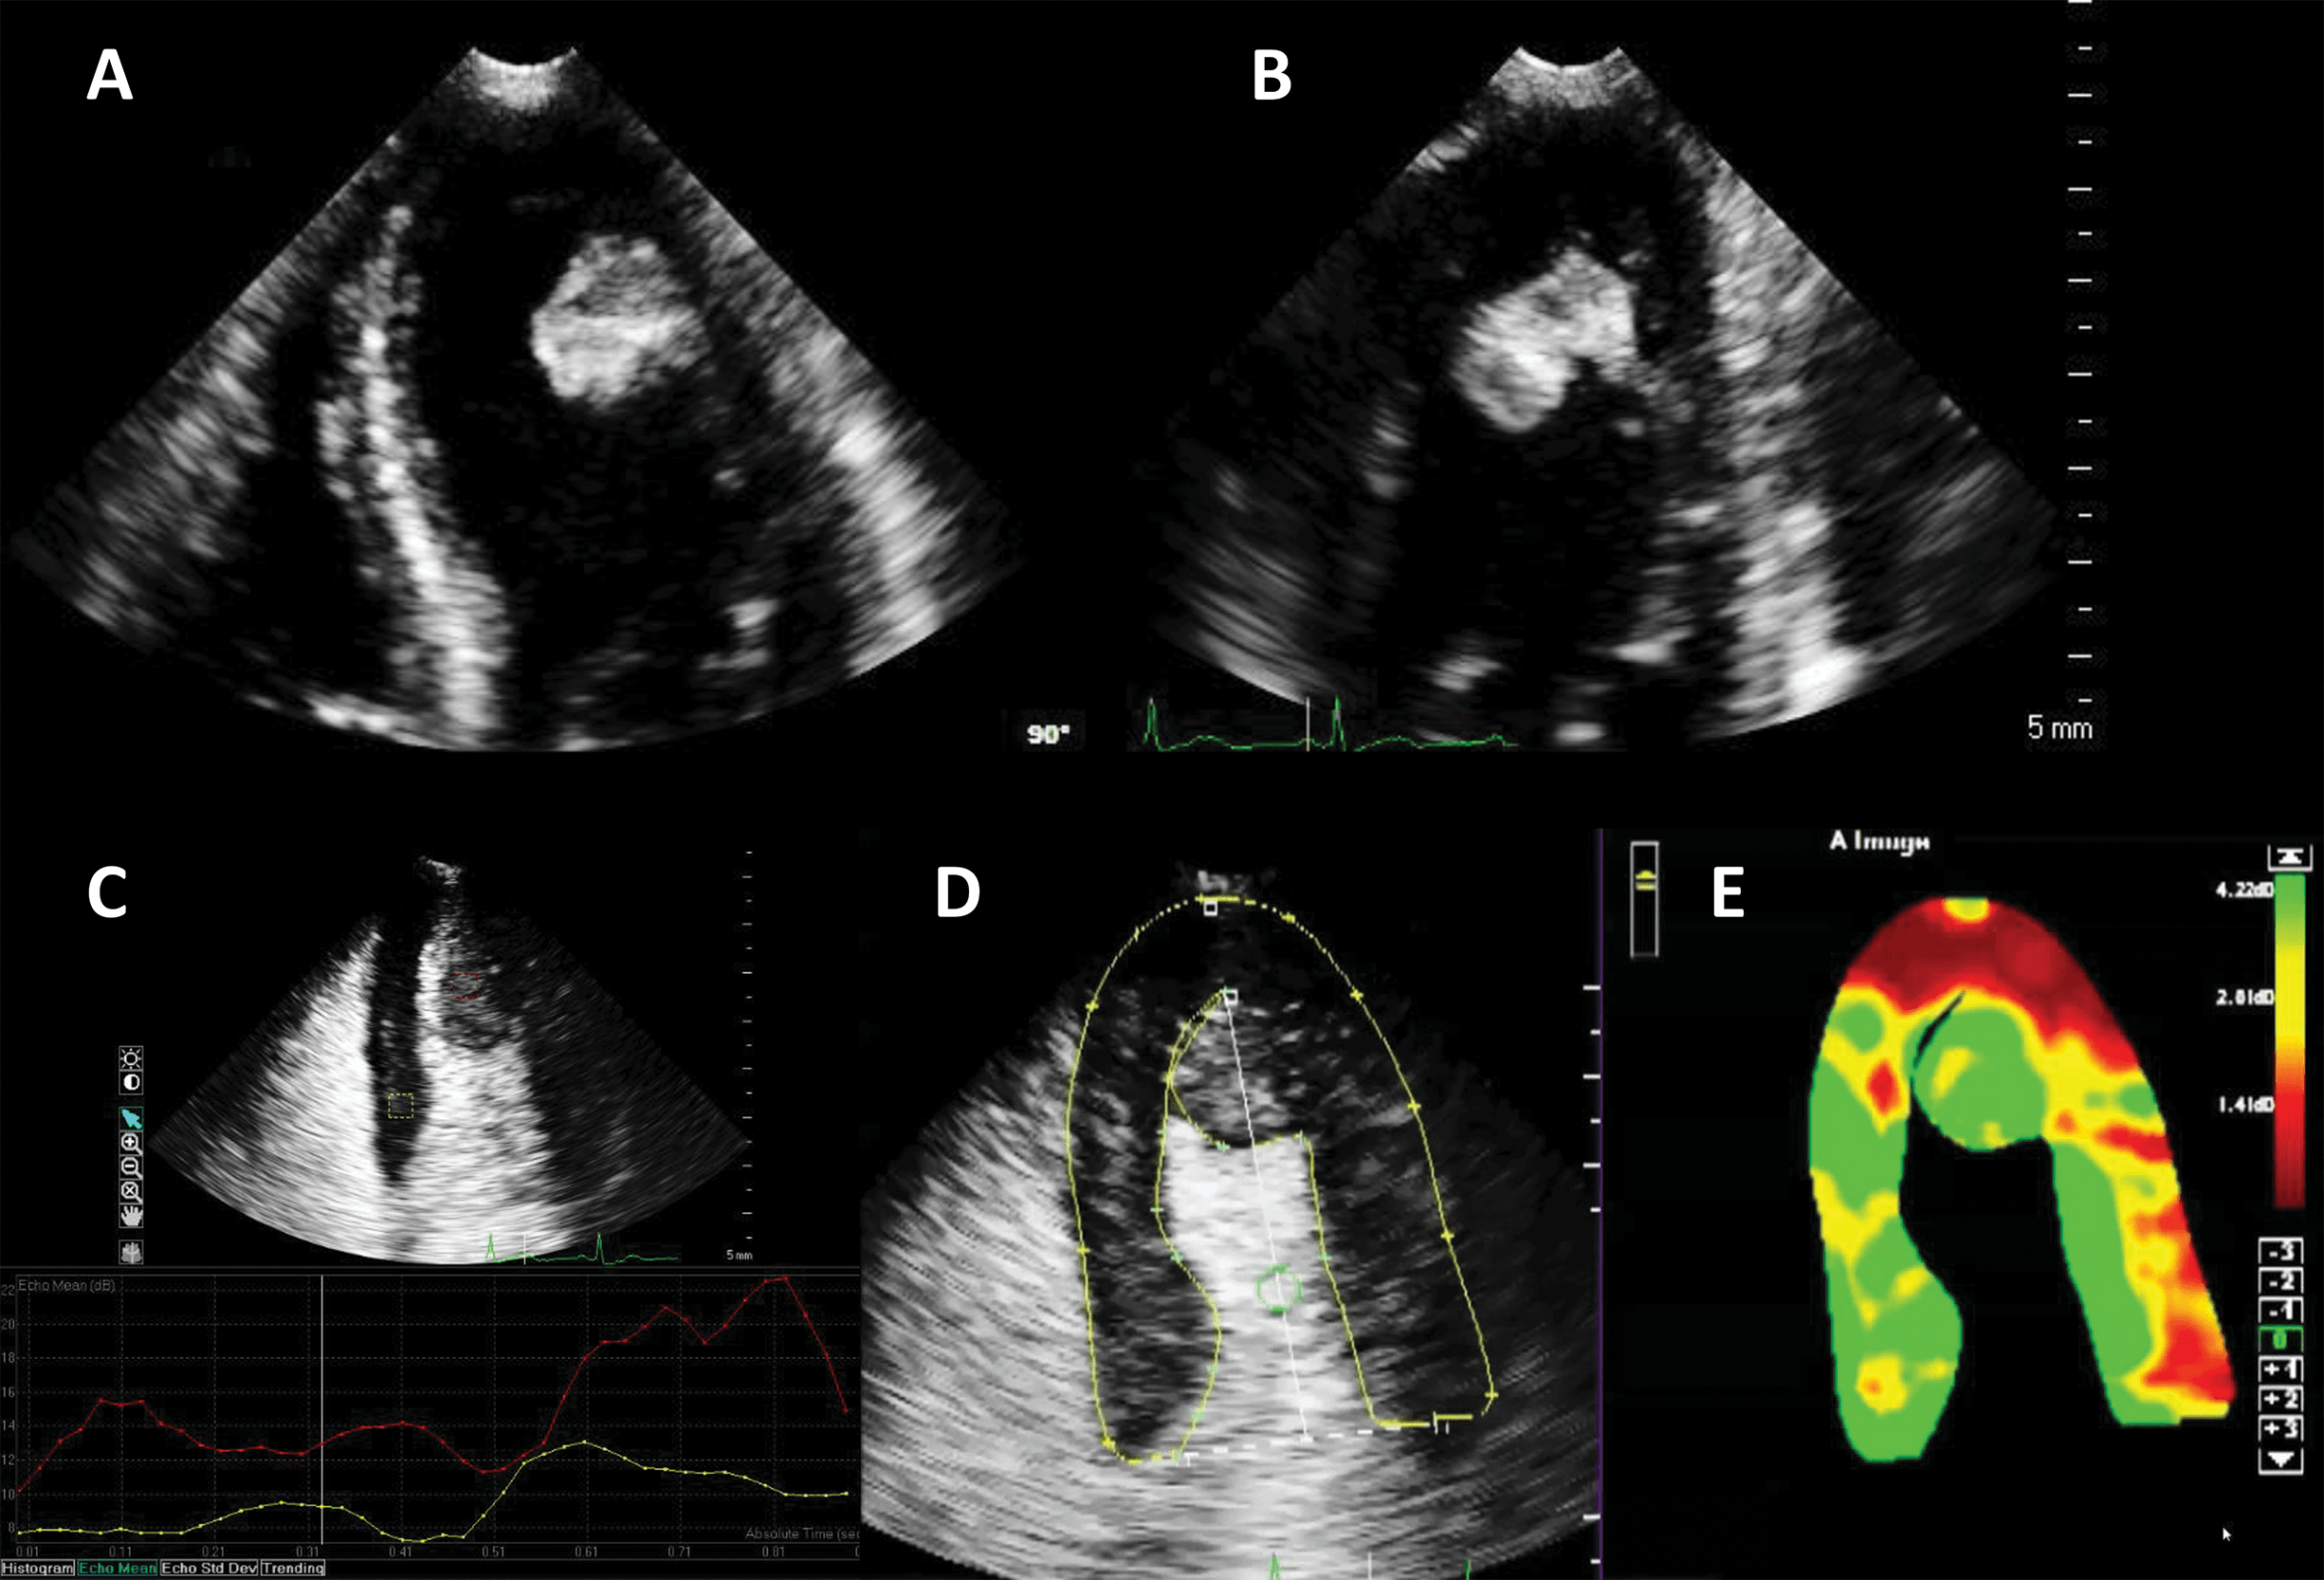

The largest body of evidence for MEE concerns the indication for LVO for enhancing the endocardial borders [10, 11, 12, 13, 14, 15]. This is achieved by using repetitive intravenous boluses of UEA, and sometimes continuous low-dose infusion. Guidelines indicate the use of LVO to enhance the endocardial borders in cases when the LV dimensions, function or regional wall motion cannot be accurately assessed using non-enhanced ultrasound [7, 14]. The general “rule of thumb” is to use microbubble UEA in cases where two or more contiguous myocardial segments are not properly visualized with non-enhanced ultrasound [13]. Of course, recent years have seen tremendous improvement in image quality for clinical ultrasound systems. But despite the introduction of harmonic imaging as a standard, some images remain non-diagnostic (Fig. 2). Moreover, harmonic imaging represented a significant leap in MEE [16, 17], leading to the present-day contrast-specific imaging modalities.

Fig. 2.Left ventricular opacification (LVO) for endocardial border delineation. Example of baseline non-enhanced echocardiography images in apical 4-chambers (A) and apical 2-chambers (B) views, where the visualization of the endocardium is suboptimal over several segments. After intravenous injection of a bolus of UEA, there is full opacification of the LV cavity, with clear delineation of the endocardium in all segments (C, D). Source: personal collection.